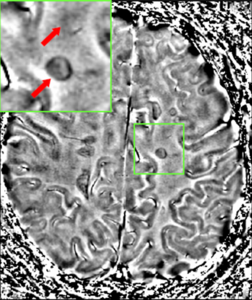

Lesions – A classic method in which a brain-region of interest is naturally or intentionally destroyed to observe any resulting changes such as degraded or enhanced performance on some behavioral measure. Lesions can be placed with relatively high accuracy "Thanks to a variety of brain 'atlases' which provide a map of brain regions in 3-dimensional "stereotactic coordinates.

The part of the picture emphasized shows the lesion in the brain. This type of lesion can be removed through surgery.